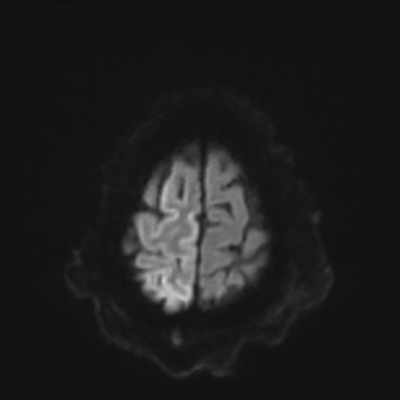

You come back the next day and see how things are going. The patient's electrographic record has shown a moderate encephalopathy (diffuse slowing, disorganization) with frequent right posterior quadrant delta slowing. Based on this result, and an adequately improved clinical examination, you give the okay to proceed with obtaining an MRI of his brain. This is shown below.

MRI brain (DWI)